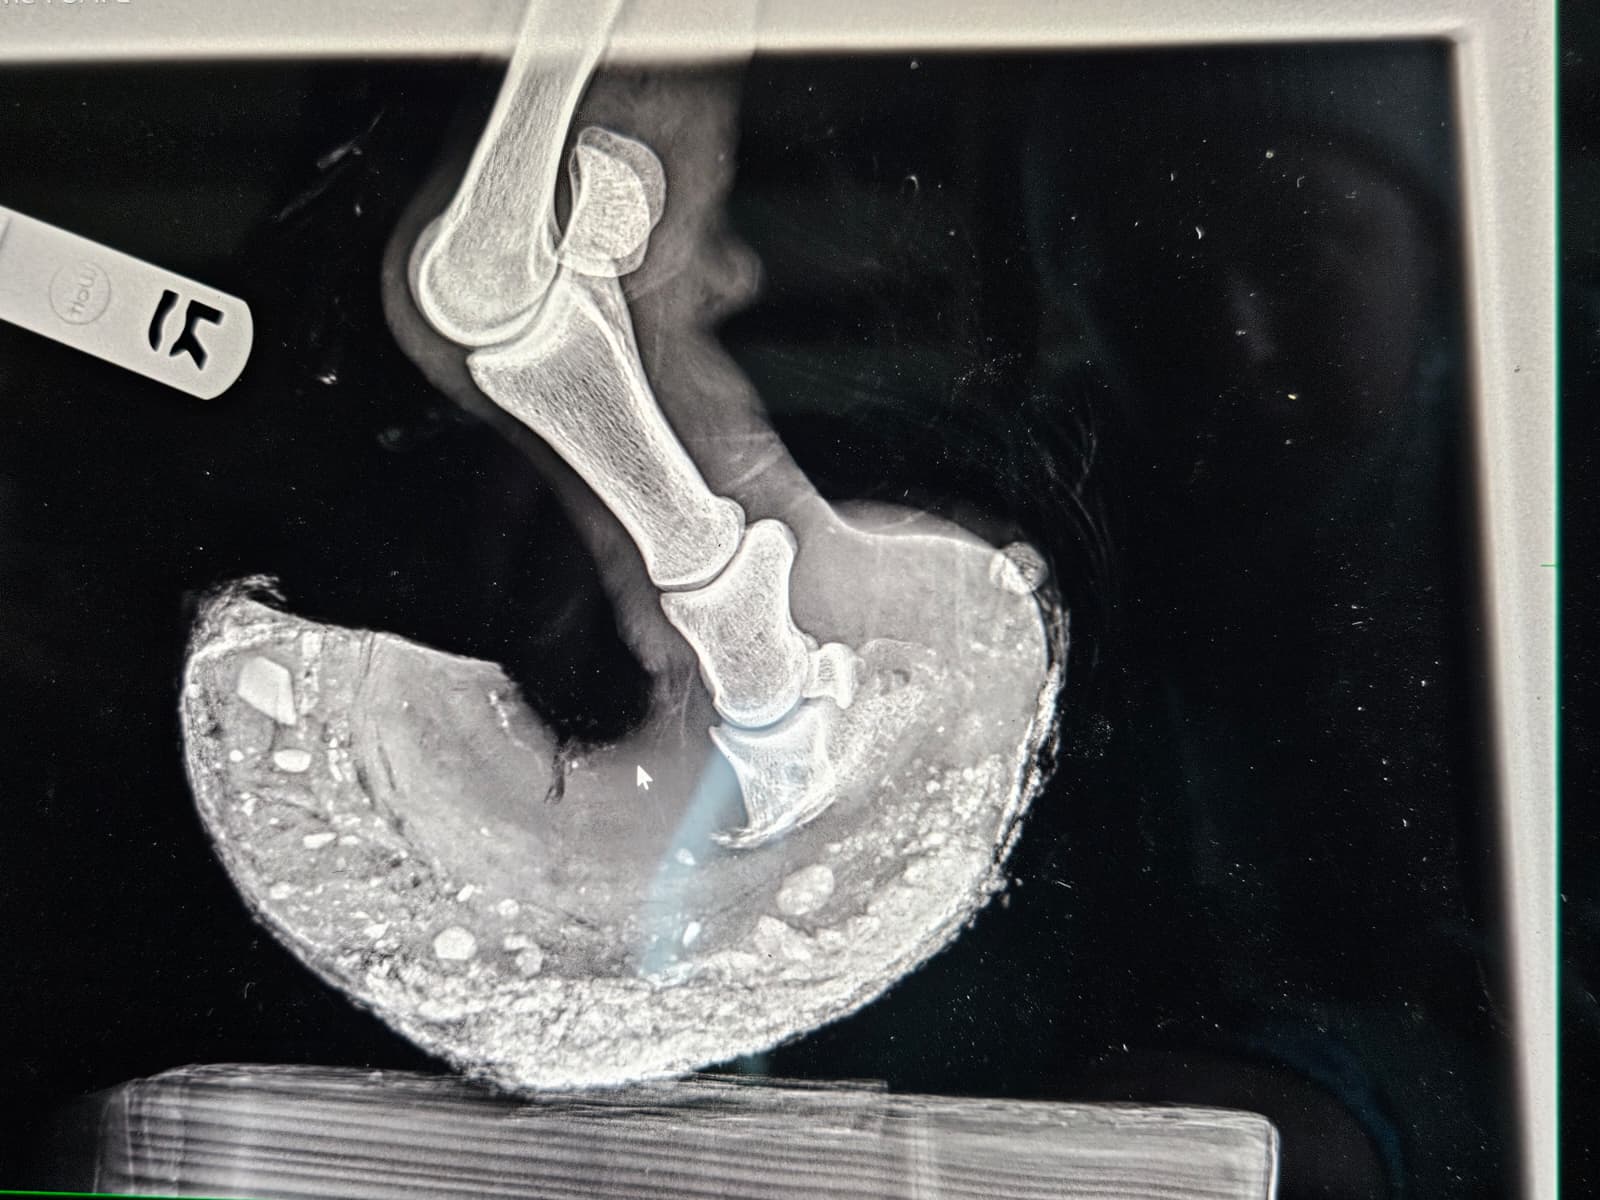

It was for our little red friend we worried the most. Hooves like hers don’t grow overnight, and the reality of what living with hooves like those does to a horse’s anatomy is at best, manageable, and at worst, unlivable. She was incredibly nervous, and required a very patient, quiet touch to allow us to sedate her for the radiographs we needed to understand what we were working with. Her small buddy accompanied her to where they had set up the x‑ray station, and stood patiently nearby as we peered under the hood.

The films revealed the depth of damage that walking on imbalanced, overgrown hooves for extended periods can do. The tips of her coffin bones were remodeling, and her hooves were severely unbalanced, with a long and deep abscess track in one of her hinds. Despite these findings, the vet was of the opinion that it might be possible to keep her and her friends comfortable with significant rehabilitation, and that all four horses were fit enough to join us back at SAFE.